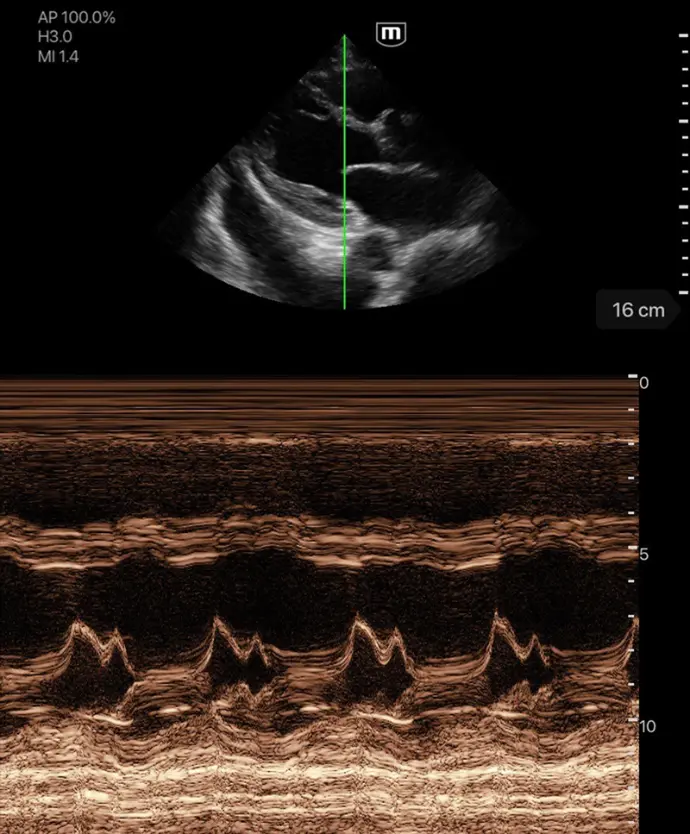

Клинични снимки

Различни режими на визуализация: B-mode, M-mode, Color Doppler, Power Doppler, PW Doppler

Различни режими на сканиране

B-режим, М-режим, цветен доплер, Power доплер и PW доплер

Множество режими на визуализация